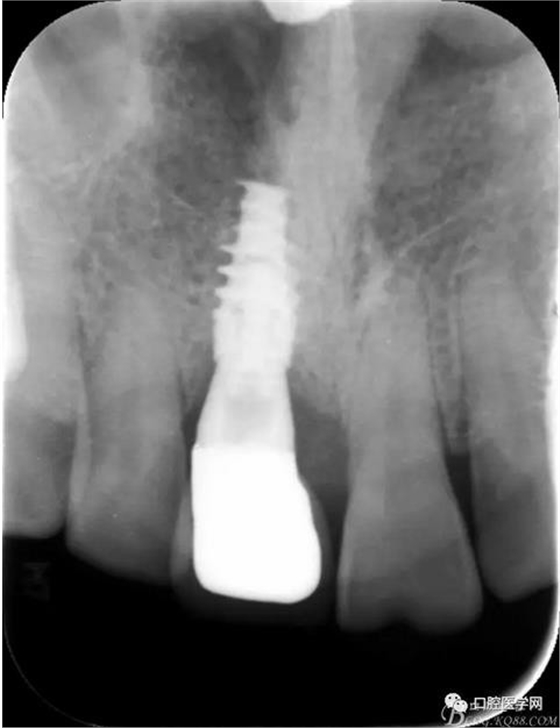

圖3 術(shù)后CT

圖24 術(shù)后 X光片